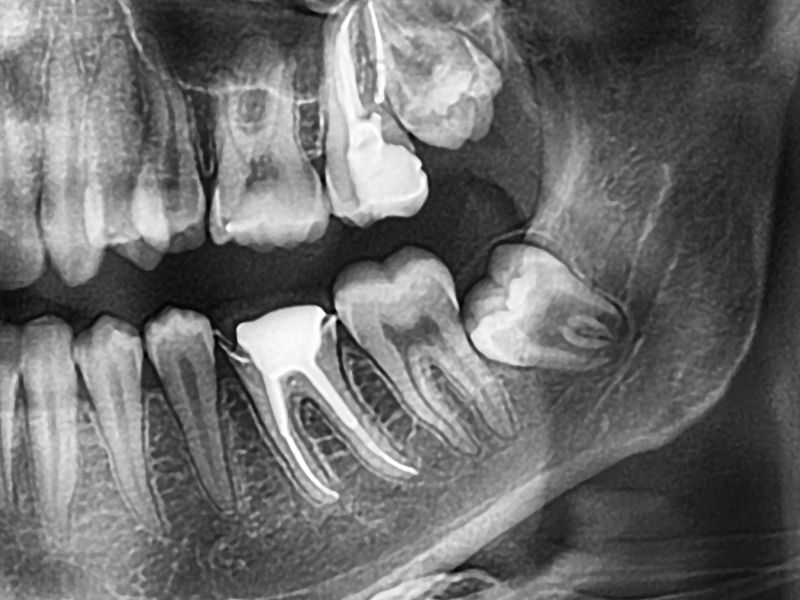

During your visit, we walk you through your X-rays and explain what your teeth are doing in plain language. The goal isn’t to rush you into treatment. It’s simply to help you understand your options for Wisdom Tooth Removal Tampa so you can make a decision that feels right.

Wisdom teeth come in long after the rest of your smile has settled. That late arrival often puts them at odd angles. Some stay stuck under the gums, some push against the molars you already rely on, and others peek through halfway and collect bacteria.

tampa fl tooth extractionsYou’ll see your digital X-rays and we’ll point out exactly what’s happening. Many patients feel more at ease once they understand the “why” behind their symptoms.